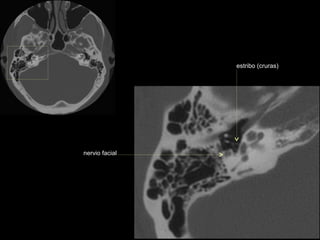

CATEDRA DE RADIOLOGIA U.N.L.P.   Hueso temporal normal              Edición 2002

seno maxilar

conducto

carotídeo

auditivo externo

protuberancia

occipital externa

trompa de Eustaquio

conducto auditivo externo

celdillas mastoideas

eminencia piramidal

seno timpánico

receso del n. facial

nervio facial (3era)

estribo (cruras)

nervio facial

ventana oval

martillo

yunque

cóclea

vestíbulo

conducto semicircular externo

articulación yunque/martillo

conducto auditivo interno

conducto semicircular posterior

antro mastoideo

celdillas retrolaberínticas

conducto semicircular

superior

conducto semicircular superior

cabeza del martillo

procidencia de meninges

tendón tensor del tímpano

conducto carotídeo

espina supra y retrotimpánica

nervio facial (2da)

nervio facial (1era)

cresta falciforme

promontorio

estribo

membrana

timpánica

externo

ventana redonda